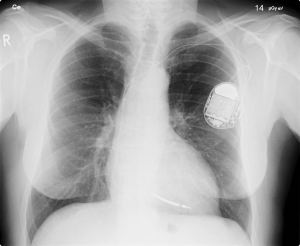

Het gaat om twee Duitse rechtszaken over de aansprakelijkheid van de producent van bepaalde types pacemakers en defibrillatoren, implanteerbare medische hulpmiddelen dus. Het Duitse Bundesgerichtshof stelt in twee separate procedures (zie BGH 30 juli 2013, VI ZR 284/12 en BGH 30 juli 2013, VI ZR 327/12) zogeheten prejudiciële vragen aan het Hof van Justitie EU over de uitleg van de Richtlijn Productaansprakelijkheid (Richtlijn 85/374/EG). Het Hof voegt de twee procedures: procedure C-503/13 betreft bepaald typen pacemakers. De andere procedure, C-504/13, betreft een type implanteerbare cardioverter-defibrillatoren (ICD).

Dit zijn de feiten.Herzschrittmacher_auf_Roentgenbild

Twee patiënten, ze worden B en W. genoemd, zijn hartpatiënt bij wie in 1999 en 2000 pacemakers van de producent zijn geïmplanteerd (de producent fuseerde later met de importeur, dus gemakshalve spreken we over de producent). In juli 2005 worden de behandelend artsen van B. en W. er door de producent op gewezen dat de hermetische afsluiting van de pacemakers mogelijk geleidelijk aan gebrekkig kan blijken te zijn. Dit kan ertoe leiden dat de batterij voortijdig leeg raakt, met als gevolg dat de pacemaker zonder voorafgaande waarschuwing stopt. Het verhoogde risico op stilvallen is naar schatting van de producent 0,17 % tot 0,51% (later bijgesteld naar 0,31 tot 0,88 %). Een deskundige stelt later vast dat het risico op disfunctioneren 17 tot 20 keer hoger dan normaal is. Om deze reden beveelt de producent aan om deze pacemakers voortijdig te vervangen. Deze aanbeveling wordt opgevolgd en de pacemakers van B. en W., die bij ziektekostenverzekeraar AOK Sachsen-Anhalt (hierna: ‘AOK’) zijn verzekerd, worden vervangen door andere pacemakers die de fabrikant gratis ter beschikking stelt. De verwijderde pacemakers worden vervolgens vernietigd zonder onderzoek naar de werking ervan. AOK, gesubrogeerd in de rechten van de patiënten, vordert van de producent schadevergoeding. In eerste en tweede aanleg wordt de vordering toegewezen, waarna het Bundesgerichtshof besluit prejudiciële vragen te stellen.

Bij de implanteerbare cardioverter-defibrillatoren (ICD) constateert de producent een soortgelijk probleem. Hier brengt het kwaliteitscontrolesysteem van de producent aan het licht dat een magneetschakelaar van de defibrillatoren in gesloten stand vast kan blijven zitten. Indien dit gebeurt terwijl de magneet juist geactiveerd moet raken, zal de behandeling van ritmestoornissen worden onderbroken. Hierdoor kan de voor patiënten levensreddende schok achterwege blijven. Voor deze defibrillatoren beveelt de producent de behandelend artsen aan – via een soortgelijk bericht als voor de pacemakers is verzonden – om de magneetschakelaar uit te schakelen. Hierop is bij patiënt F., die bij de Beriebskrankenkasse RWE (hierna: RWE) is verzekerd, de gehele ICD voortijdig vervangen. RWE, gesubrogeerd in de rechten van de patiënt, vordert vervolgens vergoeding van de kosten van de operatie waarbij de defibrillator werd vervangen. Ook hier vindt de procedure na eerste en tweede instantie haar weg naar het Bundesgerichtshof en vervolgens het Hof van Justitie.